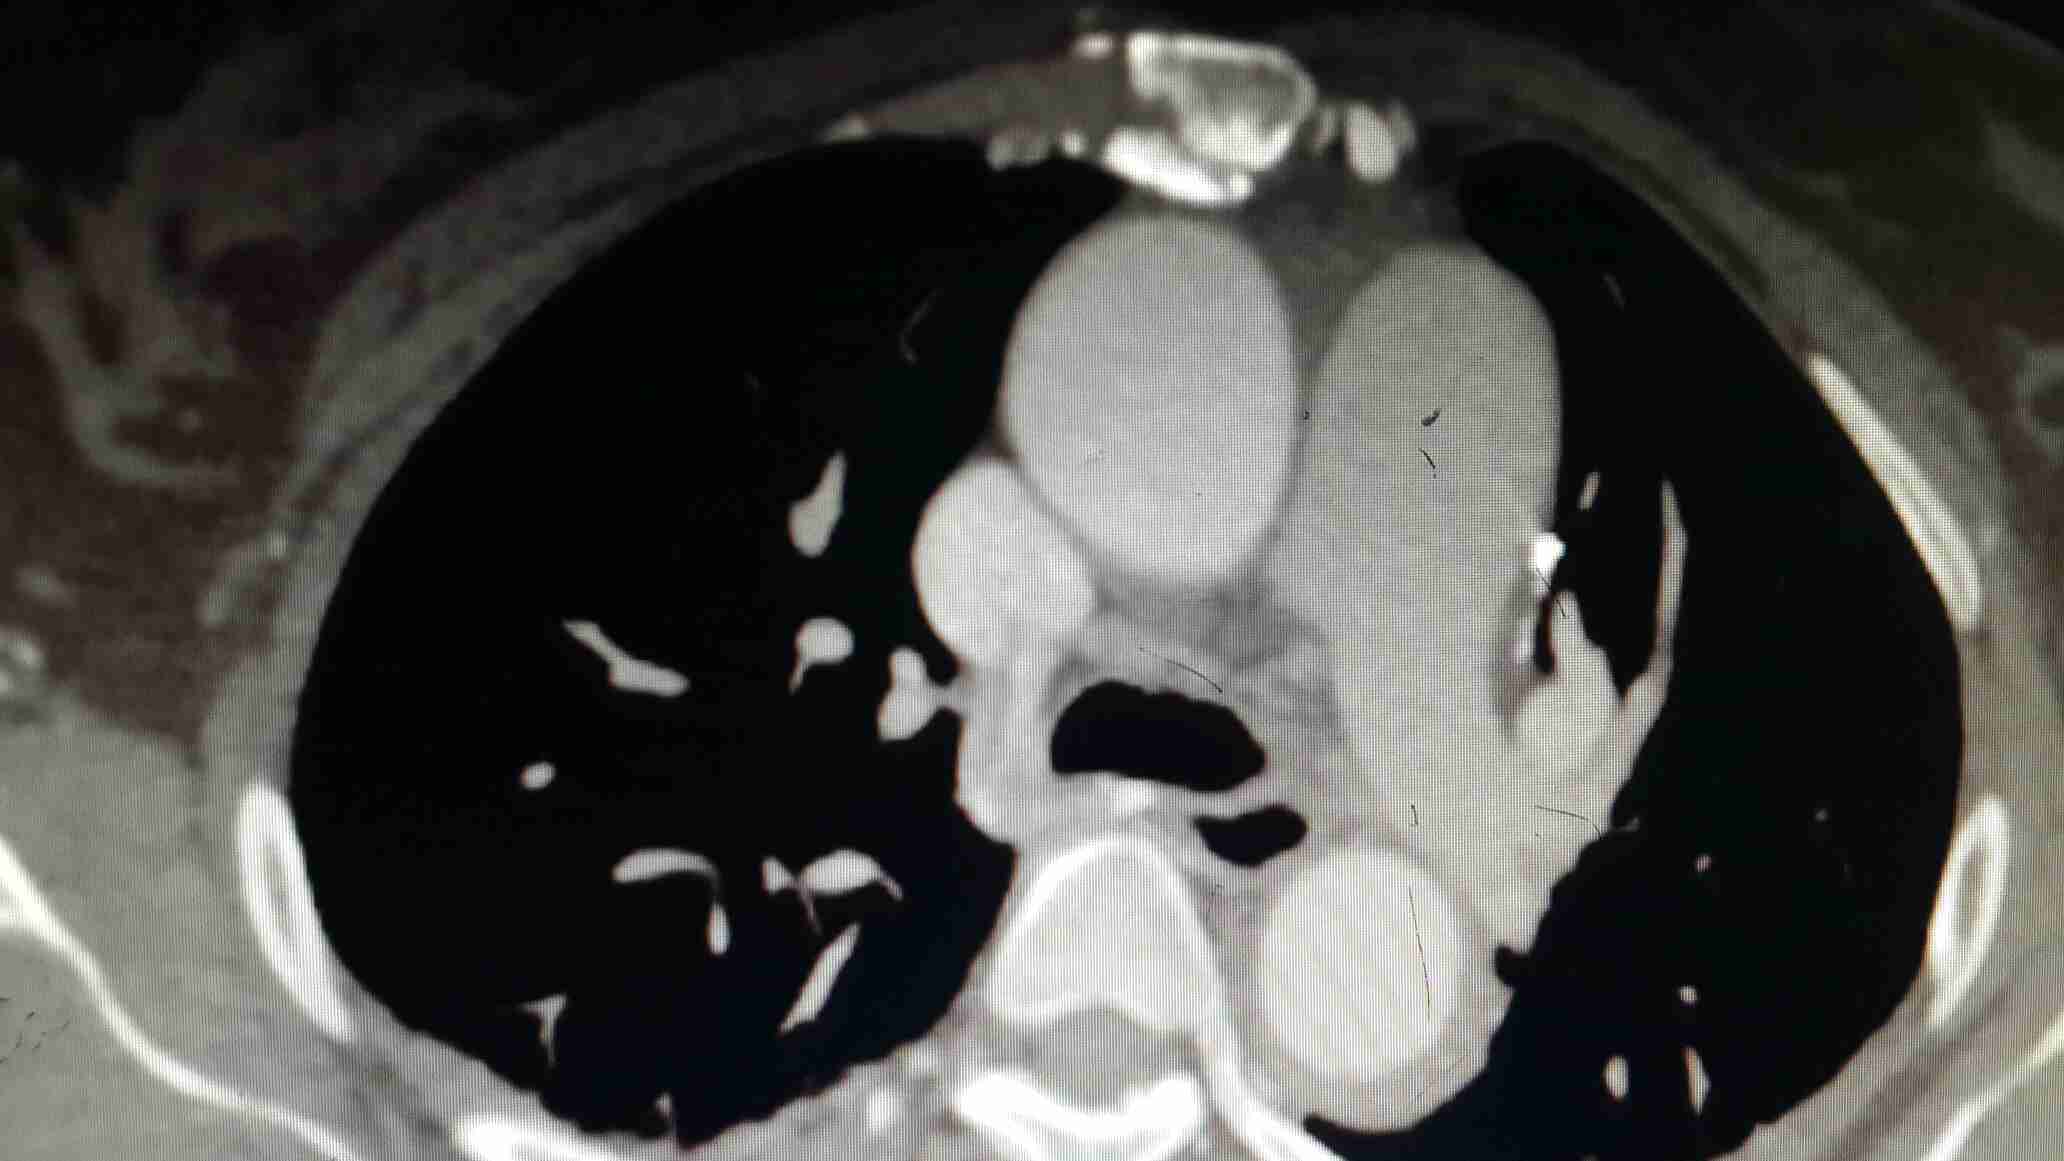

此病例是偶一年前管的一个病人,今来复诊,忽觉得其有一定的代表意义,说给大家,同时期待听到大家的不同声音,来促进学习。 患者某某,男,65岁 以“突发钻顶样胸背痛2小时”为主诉入院。 患者两小时前于情绪激动后突发钻顶样后背痛,疼痛一开始即达高峰,难一忍受忍,轻微走动后旋即又出现前胸部疼痛,性质相同,持续不缓解,伴出汗,恶心,未吐,无黑朦晕厥,无肢体活动障碍,急来我院。急诊行胸部CT后(下图),收入病房。 既往史:高血压病史10余年,最高血压180/100mmHg,未系统用药及检测。否认糖尿病史及冠心病史。有大量吸烟史,至少400年支,无药敏史。 入院时PE: T 36. 5° P 80次/分 R 22次/分 BP 180/95mmHg,其他查体未见阳性体征。 化验:CRP升高(11.8mg/L),WBC 10.3×109/L,肝、肾功,血糖、离子,血淀粉酶等正常。 心电图未见异常。急行床旁超声:主动脉瓣轻---中度返流,左室内假腱索,各心房心室不大,EF值:55% 入院后考虑主动脉夹层,紧急予以硝普钠降压,拜新同、依那普利联用口服降压,美托洛尔减弱心肌收缩力及控制心率,吗啡对症止痛,仍持续疼痛,最后经患者家属签字同意后紧急行主动脉增强CT(下图)。后疼痛逐渐缓解至平稳。 平扫CT报告:主动脉增宽,内密度不均,建议增强 增强CT:自主动脉起始部至腹腔干水平,主动脉影增宽,注药增强过程中,管壁无强化。也没有发现内膜撕裂及假腔。 请教: 您考虑的诊断?治疗? 对本病例诊治的异议?